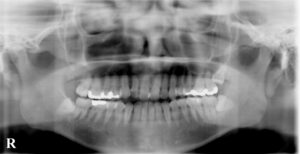

2010年1月 右上第二大臼歯の違和感で来院

明らかな虫歯の拡大ではないかとレントゲンを撮り

2017年8月 再来時に左下第二大臼歯のレントゲン

レントゲンを撮影し以前と比較説明してから

レントゲンでは神経の詰め物の状態の違い→

歯根の崩壊度は経時的なもの?→